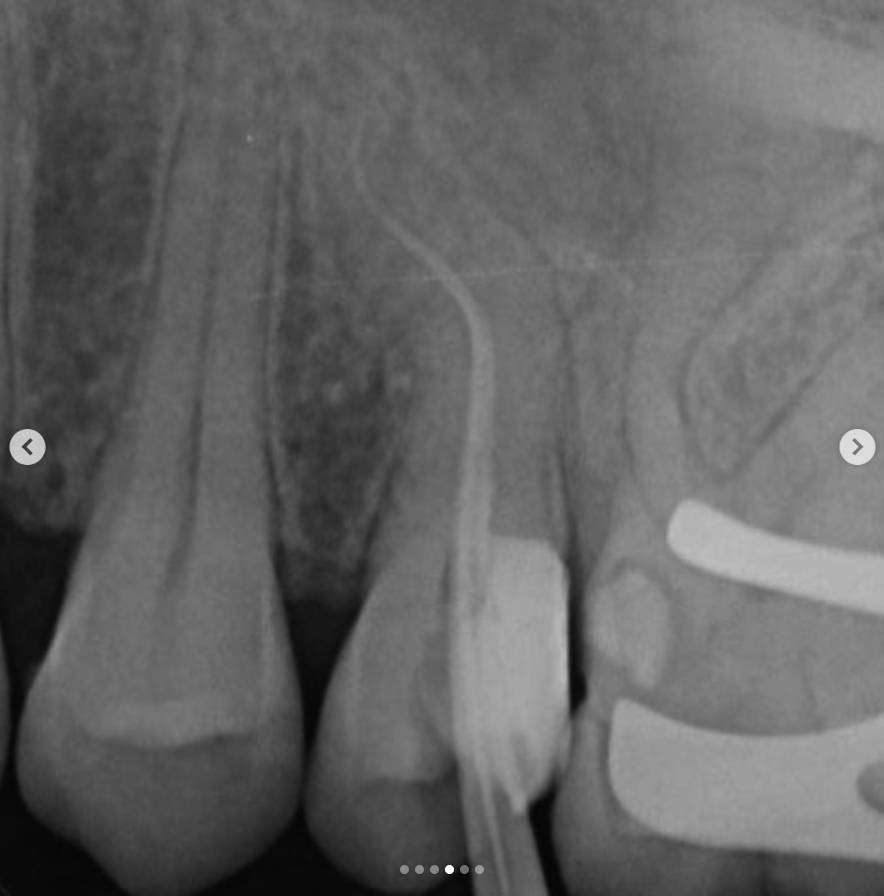

4. A working length radiograph was taken with gutta-percha cones to confirm canal length.

10/.07 → 10/.04 → 17/.05 → 25/.04

Copious irrigation and ultrasonic activation were used throughout preparation.